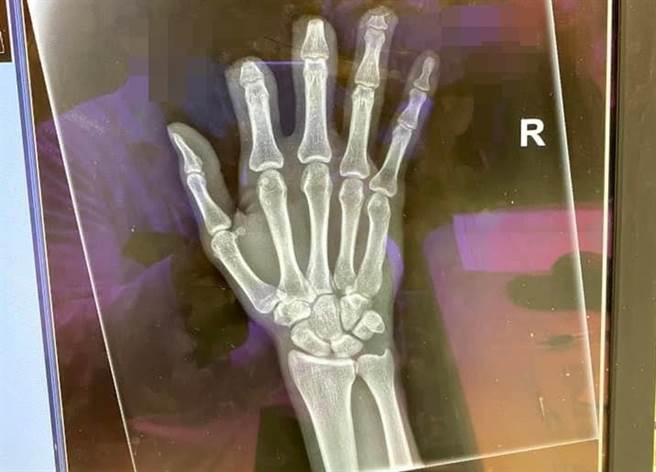

中市一名男子发生职灾,右手手指遭截肢,劳保局公文判定失能09等级(图/爆料公社)

一名网友在爆料公社发文,自己在109年12月24日发生职灾,右手手指部分截肢,工伤9个月,期间也开了2-3次手术,手还没復原,去年110年10月1日就被公司要求回去上班,但因为每周需要回诊復健治疗,主管答应不会扣薪,但实领的薪水却比工伤期间还要少,復职后还被要求归还职灾工伤期间的薪资赔偿,9个月总共35万元。